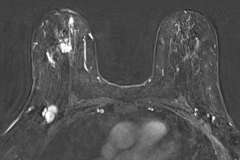

UCLA Radiology Breast Imaging Teaching Resources: Diagnosis

BIRADS:

Mammography

MRI

Ultrasound

Learn how to use BI-RADS terminology to interpret Mammograms, MRIs, and Ultrasound cases.